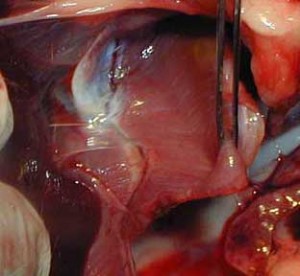

Intestines do not belong in this area, and are easily damaged when trapped in an opening this size, especially for 5 days in this case. In this picture Dr. P is carefully checking them to make sure their blood supply in intact.

Here is a different case showing the bruising and compromised blood supply that can occur when the intestines are trapped